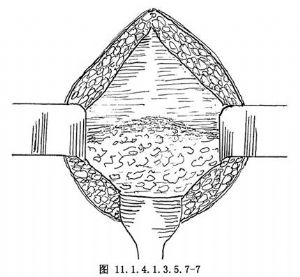

11.1 1.腹壁切開

下腹正中切口或橫切口,切開皮膚、皮下脂肪、腹直肌前鞘,暴露腹膜前間隙(圖11.1.4.1.3.5.7-7)。